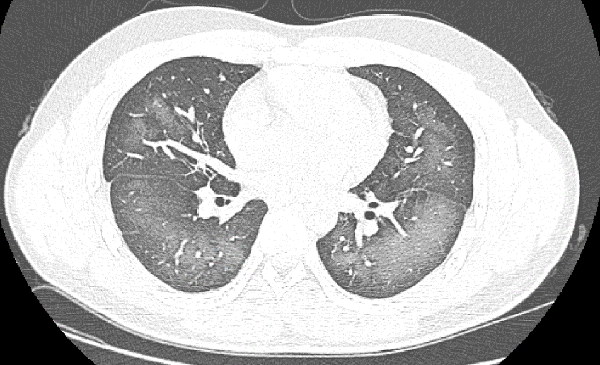

??? ?? ? CT ???? ??? ?? ?? ???? ?? ??? ??? ???? ‘??’?? ?????.

‘??’? ????? X? ?? CT ???? ?? ??? ??? ???? ??? ?? ?? ????, ???? ? ?? ??????? ???? ???? ?? ??? ???.